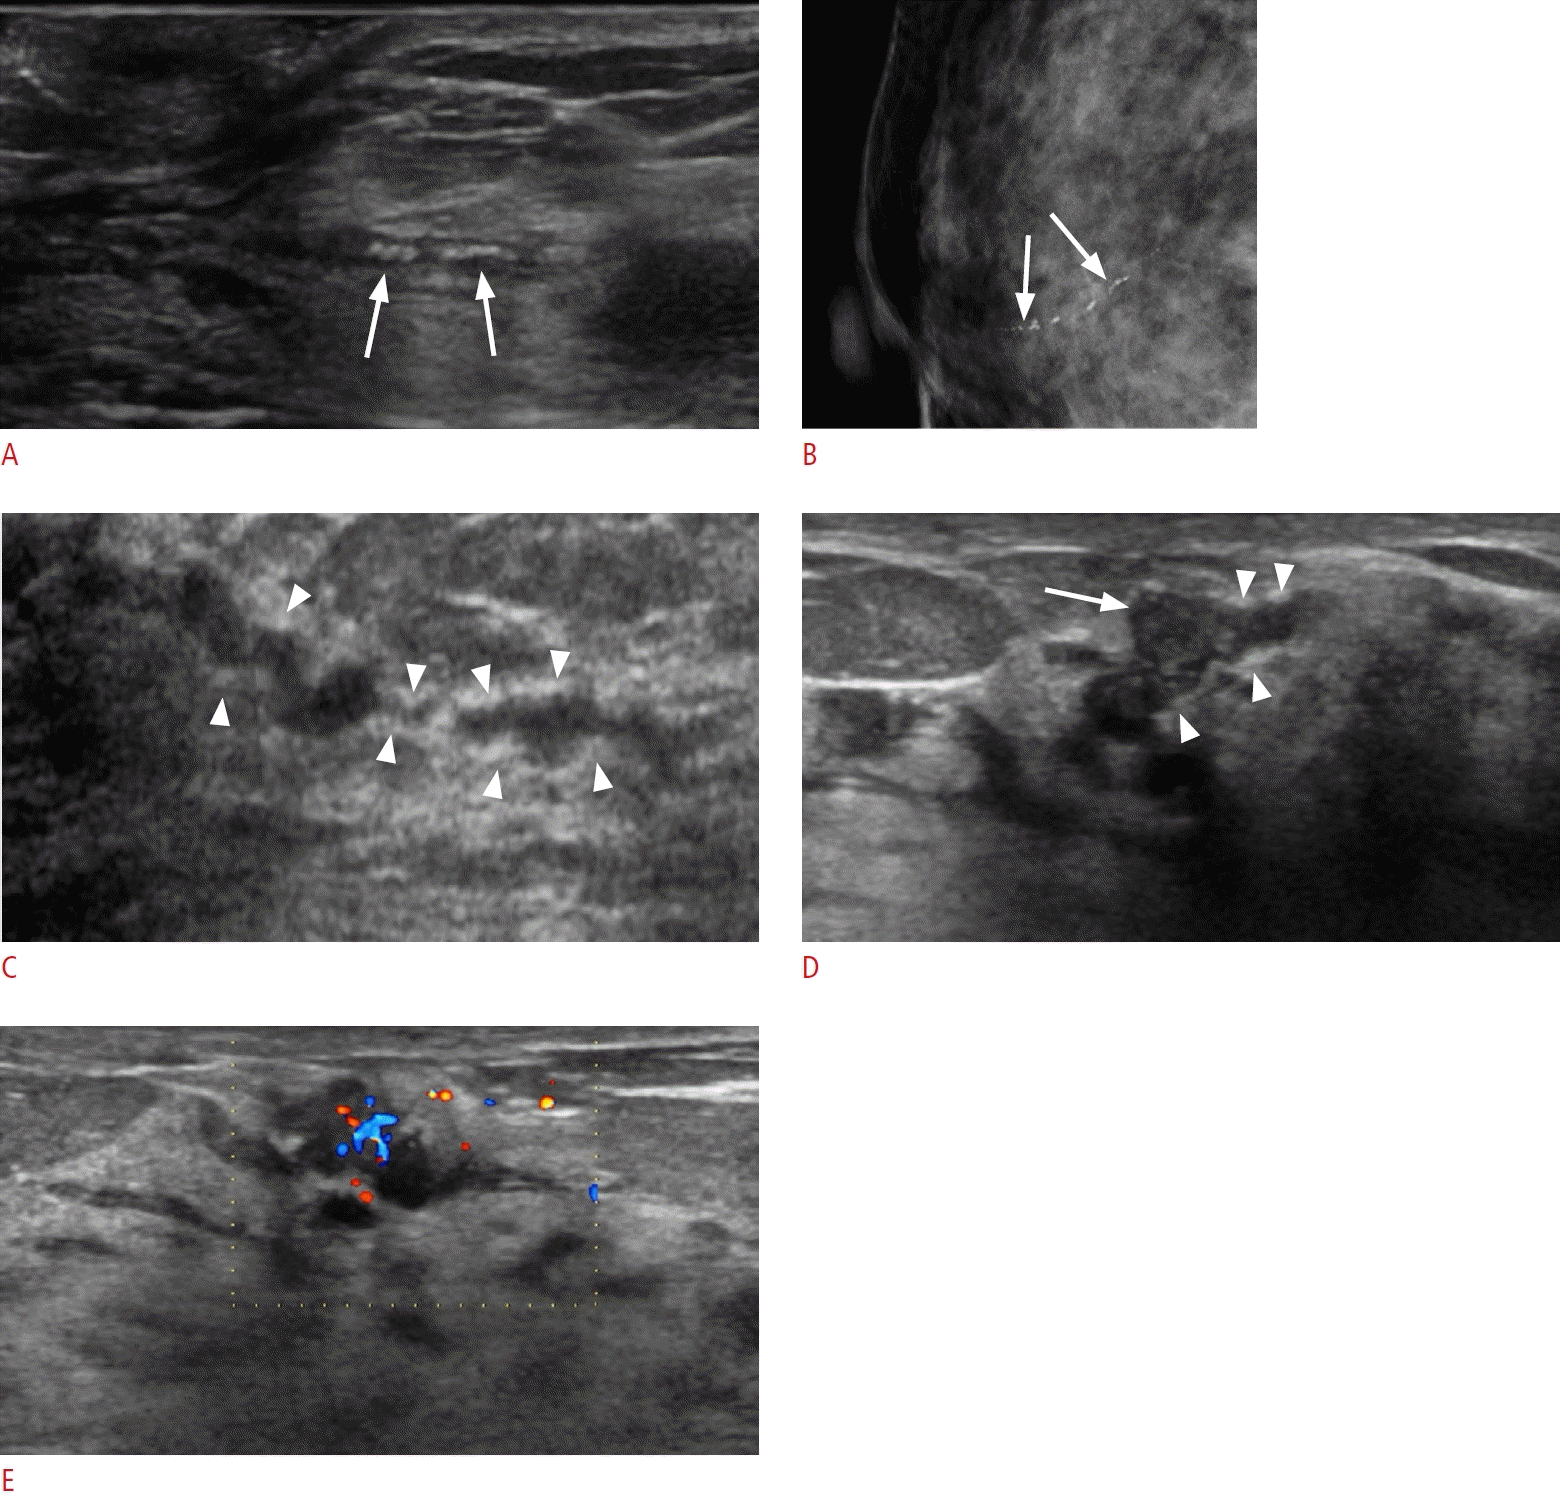

32. Okuno T, Watanabe T, Yamaguchi T, Konno S, Takaki R, Watanabe R, et al. Usefulness of color Doppler and strain elastography adjunctive to B-mode ultrasonography in the diagnosis of nonmass abnormalities of the breast: results of the BC-07 multicenter study of 385 cases. J Med Ultrason (2001). 2025; 52:157–168.

4. Kim KW, Cho KR, Seo BK, Whang KW, Woo OH, Oh YW, et al. Sonographic findings of mammary duct ectasia: can malignancy be differentiated from benign disease? J Breast Cancer. 2010; 13:19–26.

5. Song SE, Yie A, Seo BK, Lee SH, Cho KR, Woo OH, et al. A prospective study about abnormal ductal dilatations without associated masses on breast US: what is the significance for us? Acad Radiol. 2012; 19:296–302.

47. Boonjunwetvat D, Rengganis AA, Manasnayakorn S, Vongsaisuwon M, Tantidolthanes W, Sampatanukul P. Sonographic focally thick duct of breast found in screening, why is it concerning? A report of three cases. Breast Dis. 2022; 41:215–219.